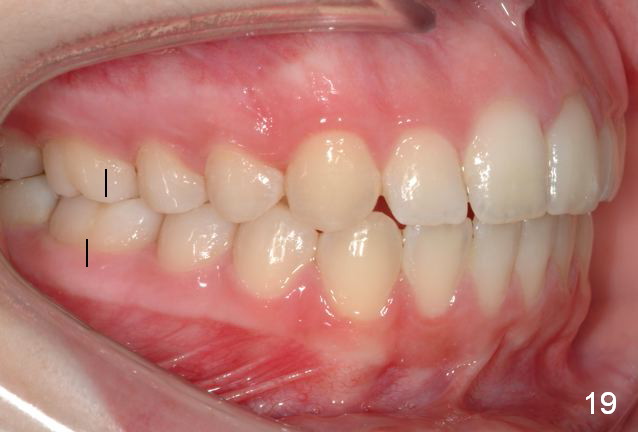

Final Results of Unilateral Class II Malocclusion

After using Rapid Molar Distalizer.  Total treatment lasts 50 months.